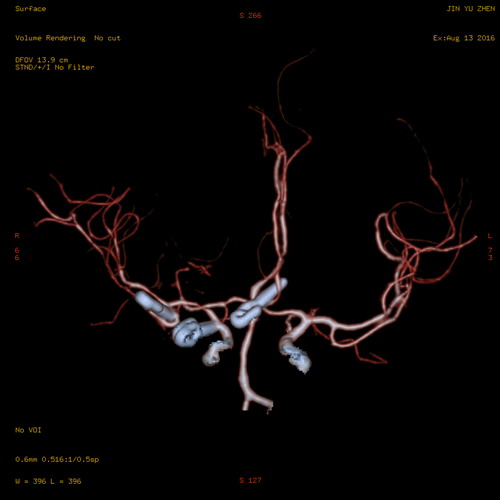

图为患者术后CTA检查提示右后交通动脉瘤瘤夹、右大脑中动脉瘤瘤夹、前(偏左)交通动脉瘤瘤夹

该患者因突发剧烈的持续性头痛,且感到左手指末端麻木不适,前往当地医院就诊,被诊断出蛛网膜下腔出血。随后转院至临床医学院/附属医院进行治疗,行全脑血管造影术显示右后交通动脉瘤、右大脑中动脉瘤、前(偏左)交通动脉瘤及右大脑中动脉中到重度狭窄。考虑到颅内三处动脉瘤随时可能发生破裂而危及生命,手术及其复杂而且风险性非常高,神经外科赵浪平主任立即组织全科医生讨论,制定最佳手术治疗方案并征得家属同意。

据陈亮副主任医师介绍,颅内多发动脉瘤破裂出血机率较单个动脉瘤大,出血更为凶险,死亡率更高,即使介入手术或者开颅夹闭手术也容易出现术中大出血或死亡等情况,因而此类患者一旦诊断明确也只能冒险进行手术治疗,否则如果动脉瘤再次破裂出血便回天乏术了。